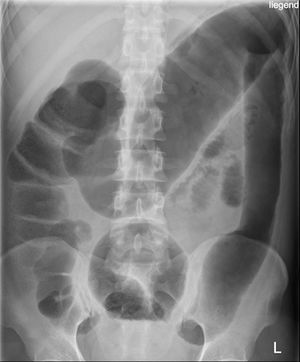

Toxic megacolon on KUB

• Diameter ≥6cm with gaseous content